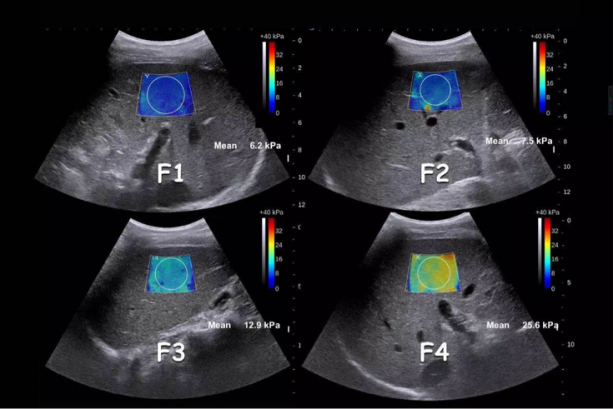

图1

如上图所示,颜色由蓝到黄,杨氏模量测值由小到大,表示了慢性肝病患者从F1期(轻度肝纤维化)到F4期(肝硬化)肝脏硬度的改变

E成像技术用于测量肝脏组织硬度,可应用于各种慢性肝病包括肝纤维化、肝硬化、脂肪肝的定量检测。不需做特殊准备,仅需在常规超声检查基础上叠加剪切波成像技术,就可精准、迅速的获得纤维化病变处的硬度即杨氏模量。杨氏模量值越高,代表该病变处硬度越大,纤维化程度越严重,使肝纤维化与病理相关性更强,并可以依靠此定量依据进行临床治疗及治疗方案的调整。E超的出现弥补了常规检查的不足,具有无创、定量、可重复性高的优点,不仅如此,通过E超测量肝脏、脾脏硬度,可以评估门脉高压并发症的发生风险。